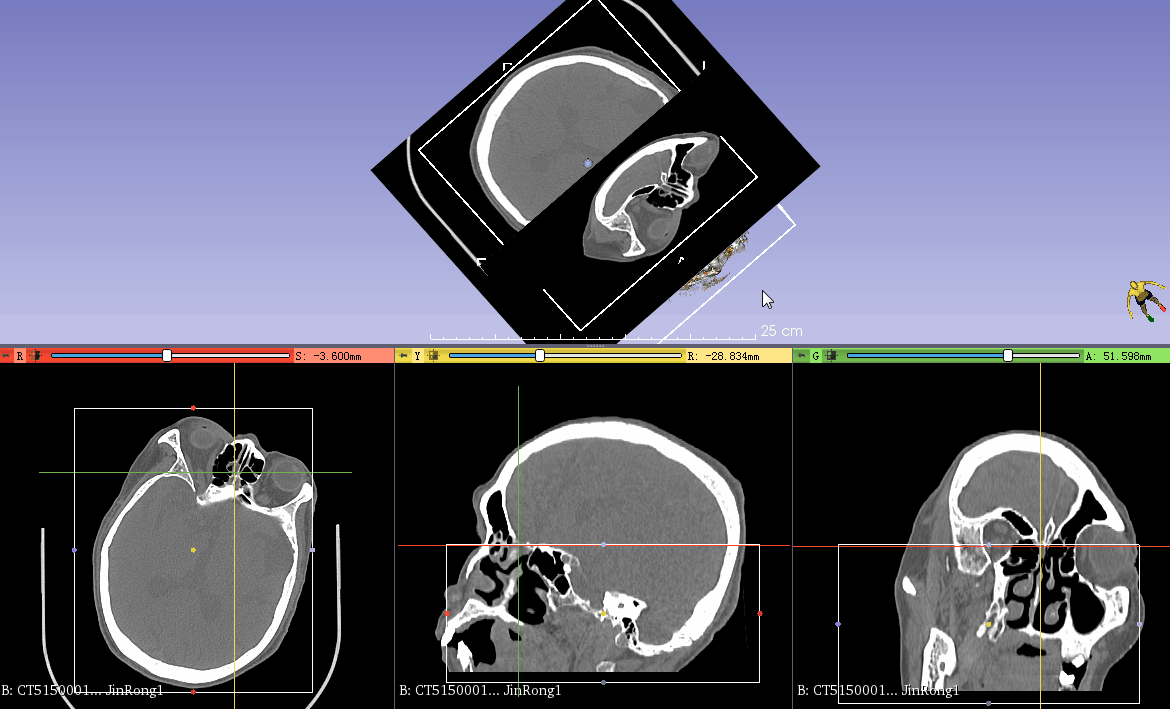

进一步三维CT阅片与重建,导航般了解患者病变位置,患者瘘口位于筛前动脉水平——筛板,嗅凹。

动态观察瘘口位置,制定详细的手术计划。

经鼻腔内镜手术难度虽然不大,但是在狭小空间里取得足够的操作空间也并不容易;其次,鼻腔气房结构的复杂性让人望而生畏。无论是手术过程中无法寻找到漏口的焦躁,还是术野出血的紧迫感都会让医生倍感压力,但是如果术前能够准确定位(三维导航般阅片,三维影像的模拟重建),术中按部就班,依照解剖结构按图索骥,必然获得最终手术的成功。